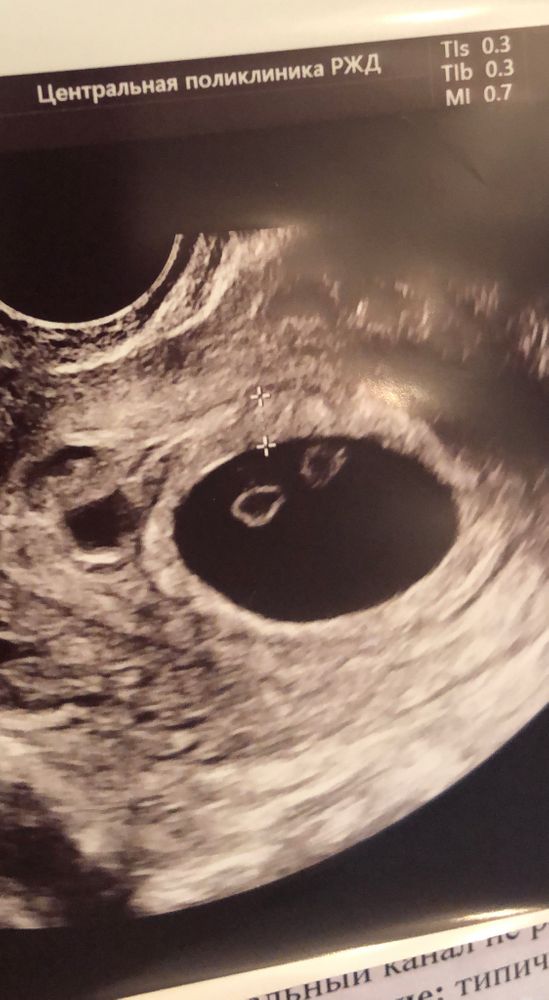

Мои поздравления! Мне всегда казалось почему то, что у вас двойня)) видимо знак)) Обязательно вступайте в наши сообы- многоплодная беременность и двойняшки. родившие девочки все консультируют, рассказывают, очень много полезной информации там найдёте 🙌🏻 все таки многоплодка это особый случай:) У меня была моно ди двойня, соответственно близнецы. вот я не поленилась и нашла первое узи - действительно не отличишь от ди ди, это прояснится уже позже.  Изображение сразу по всему напишу: про хгч: у меня был низкий. Вот прям низкий и рос плохо, и ничего это не означало. про токсикоз: у меня был птздц😗, очень плохо мне было. И долго. Было плохо очень долго..) мне как-то сказала врач, что если в предыдущие б был токс, то скорее всего повторно будет, это особенность организма, а не беременности. про ицн: очень, очень и очень плохая предыстория для двойни. Конечно с шейки вам глаз не спускать придётся.. опять же, по словам врача, это тоже особенность организма. Но двойня это фактор, который повышает вероятность ицн для любого организма, поэтому… скорее всего ицн повторится, надо просто вовремя принять меры. насчет переживаний: двойня это крайне непредсказуемая история… может не развиваться, может замереть, может отставать. Может понадобится экс, может быть ер, могут пересидеть и получится перерастяжение матки, а могут родиться преждевременно и кстати вероятность очень высока, учитывая ицн. Вы извините, что это все говорю, но вы девушка умная и должны понять. чем скорее вы эти риски примите как данность, тем вам будет лучше. Иначе от узи до узи будете сходить с ума) а от всего остального вообще никто не застрахован. так что не бойтесь, все вопросы решите по мере поступления. Главное, отдайтесь лучшим врачам, я настоятельно рекомендую Кулакова, Кирилл Витальевич Костюков узи эксперт по двойням, не пожалейте денег наблюдаться у него. Врачи все хорошие, я была у Гладковой, многие девочки у Тетруашвили, у Грачевой и других, спокойно выбирайте. Удачи!!! 🍀

Елена, да, возможно, хотя в заключении узи пока пишут диди, но, я так поняла, что от моноди ее сейчас не отличить) мама моей подруги, акушера-гинеколог, тоже считает, эьо это близнецы) Спасибо!) будем стараться помочь малышам дорасти до срока и появиться на свет здоровыми и счастливыми✊